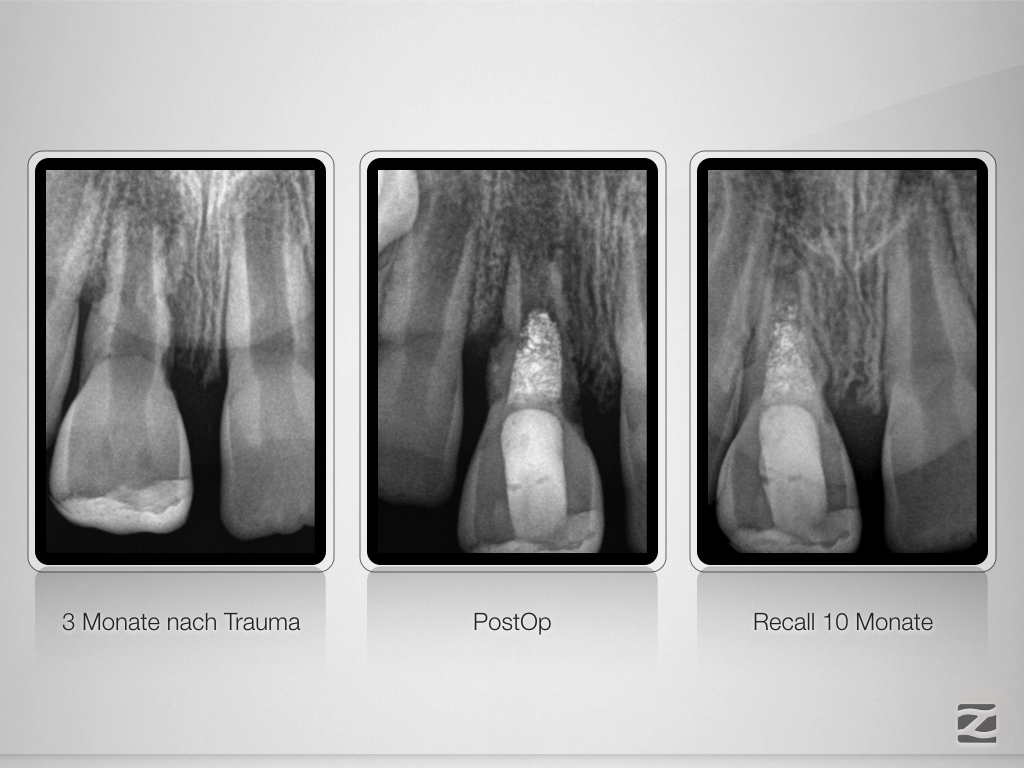

Bestmöglicher Kompromiss